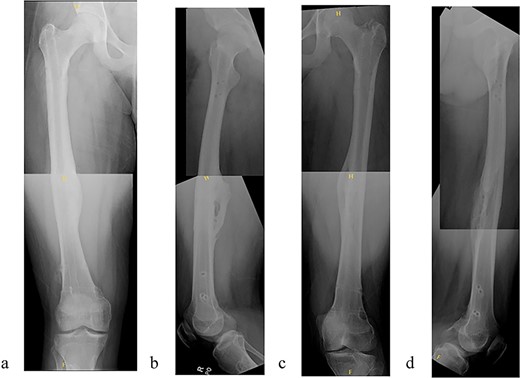

A 14-year-old boy sustained closed right and left mid-shaft femur fractures (Right OTA 32-A3, Left OTA 32-B2) after an all-terrain vehicle accident (Fig. 1a and b). The patient was classified as obese with a BMI of 37. Bone age was determined to be approaching skeletal maturity and so a rigid trochanteric entry femoral rod was selected for the implant [15, 16] (Fig. 2). Laboratory derangement included hyperphosphatemia and hypoalbuminemia. Therefore, additional measures to include early fracture stabilization and the RIA adjunct was selected for our patient [17].

(a) Right femur fracture (OTA 32-A3). (b) Left femur fracture (OTA 32-B2).